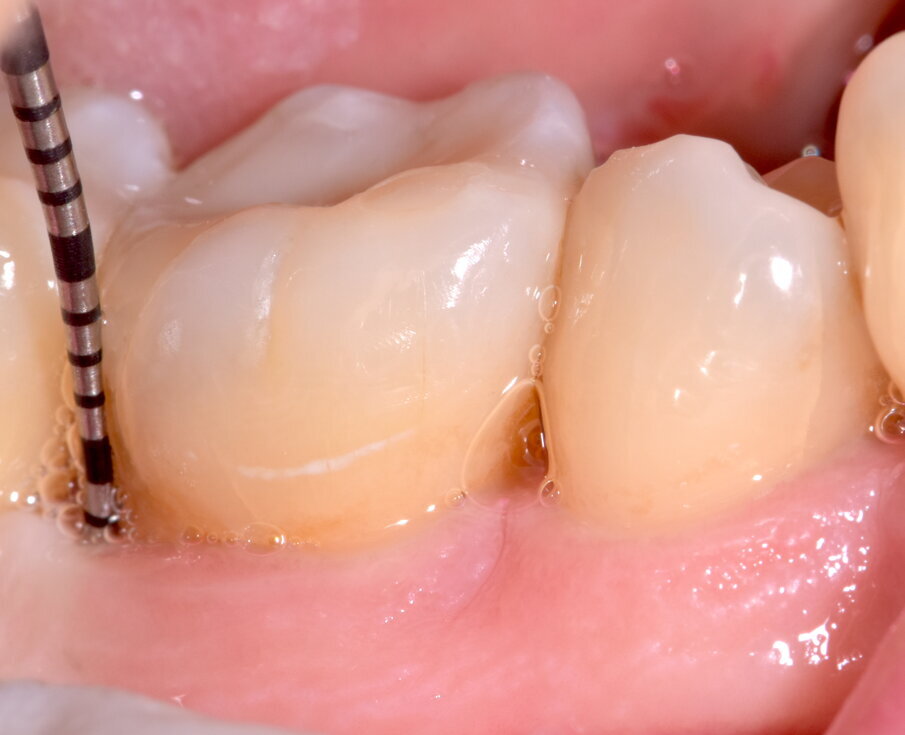

Fig. 4 - Sondaggio DV dell’elemento 4.6 di 9 mm.

Fig. 14 - Maturazione dei tessuti e sondaggio a 3 mesi.

A 3 mesi dell’intervento il sito viene valutato nuovamente attraverso ispezione clinica e indagine radiologica; i tessuti molli risultano sani all’aspetto e al sondaggio (assenza di SOP e BOP, sondaggi MV dell’elemento 4.7 e DV dell’elemento 4.6 rispettivamente di 3 e 4 mm) ed i tessuti duri appaiono re-mineralizzati in radiografia, con il difetto intra-osseo completamente ricostruito. Distalmente all’elemento 4.6 si osservi come la papilla interdentale si sia invaginata durante il periodo intercorso tra la rimozione sutura e il controllo a 3 mesi, ciò è dovuto all’utilizzo da parte della paziente di uno scovolino di dimensioni non adeguate che viene prontamente sostituito. Anche dopo la chirurgia, la paziente rimane un soggetto con Periodontal Risk Assessment alto, a causa della perdita ossea e di elementi dentari rapportata con l’età, pertanto si inserisce in un programma di richiami trimestrali di igiene orale professionale in modo da ridurre al minimo il rischio di recidive.